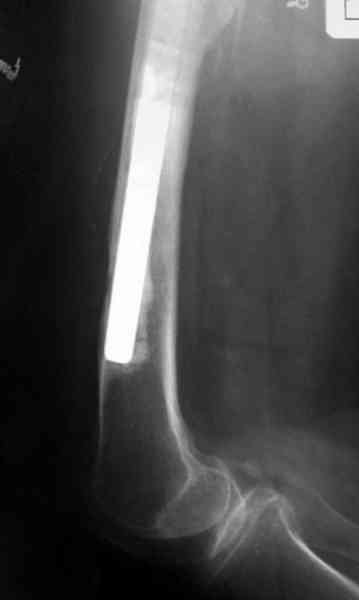

Для спейсера в бедро использовал старый длинный бедренний компонент меньшего диаметра, облепленный со всех сторон цементом с антибиотиком.

№3-6 снимки с осложнением